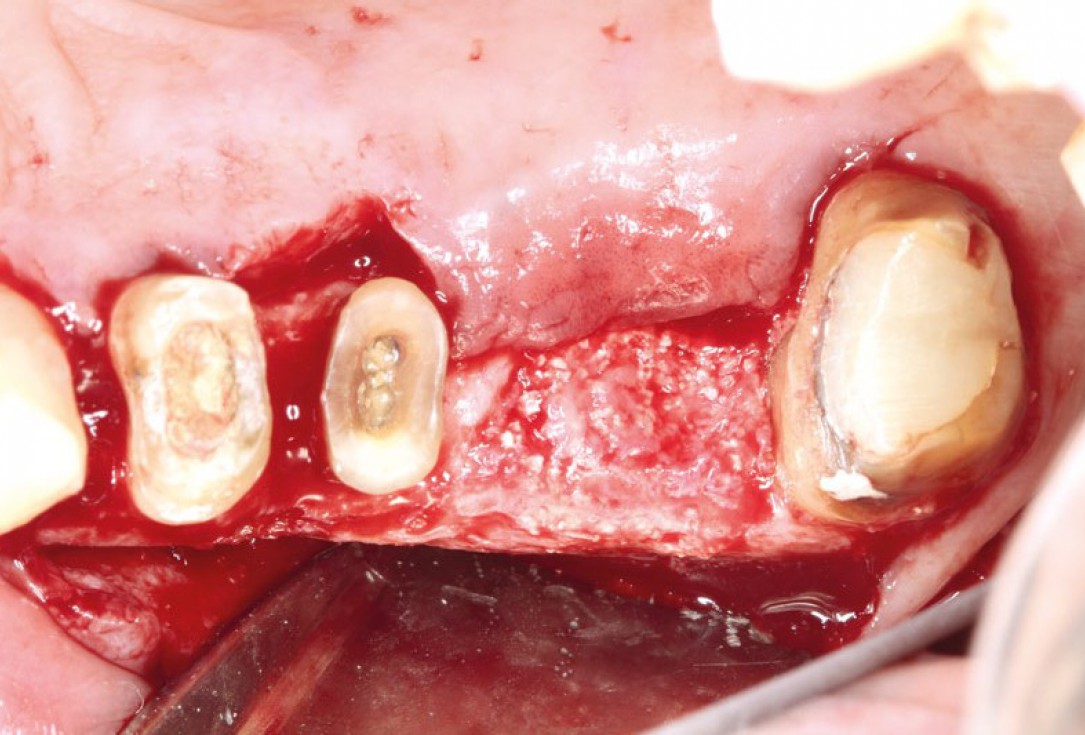

botiss-cerabone-permamem-maxgraft-mucoderm-horizontal-gbr-maghaireh

Initial situation - A young female 34 years old lost her front teeth in an surfing accident and she had a 5 unit bridge supported by her upper left lateral and right canine. The restoration failed and both supporting crowns have exposed and leaking margins.